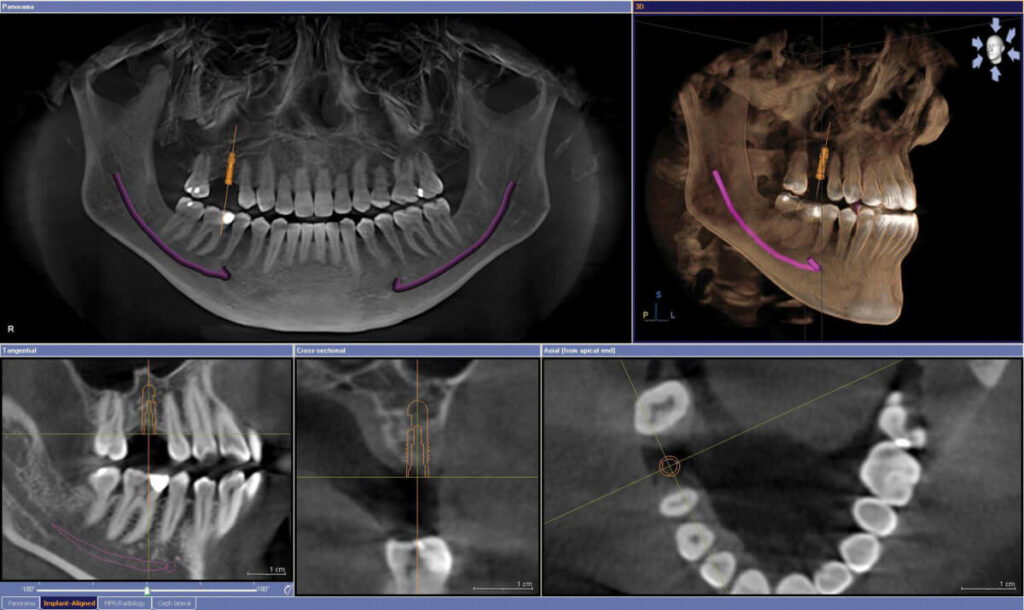

10 ЧИГЛҮҮЛЭГЧТЭЙ ШҮДНИЙ ИМПЛАНТ СУУЛГАХ (Guided surgery)Цааш унших… 10 ЧИГЛҮҮЛЭГЧТЭЙ ШҮДНИЙ ИМПЛАНТ СУУЛГАХ (Guided surgery)